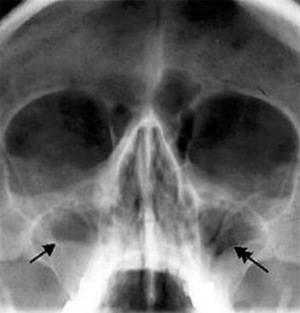

Сфеноидит (рентгенограмма)